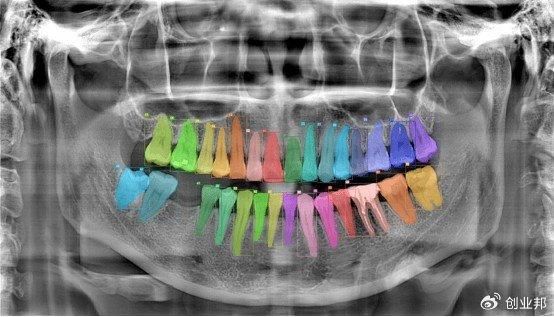

数字化诊疗场景以CT为入口,目前已经实现常规诊断,使用AI介入后,10秒钟能够完成34种常规疾病的诊断和治疗计划,让医生在电脑、PAD、手机上都可以看到诊断和治疗计划,并通过手术导航机器人辅助医生完成手术。

图/基于登特菲原子引擎AI+TV-MAR智能CT算法的诊断建议报告(部分)

黄开先举了一个例子,目前登特菲推出的AI已经可以辅助医生通过CT影像自动生成整体种植诊断以及对应的种植方案,并将方案同步至手术导航机器人。机器人可以配合医生,在患者口内,按照CT规划方案执行种植手术。从影像、诊断、治疗计划到最后实施手术,全链路实现智能化,大大提高了医生的工作效率,节省宝贵时间,更专注于患者的诊疗工作。